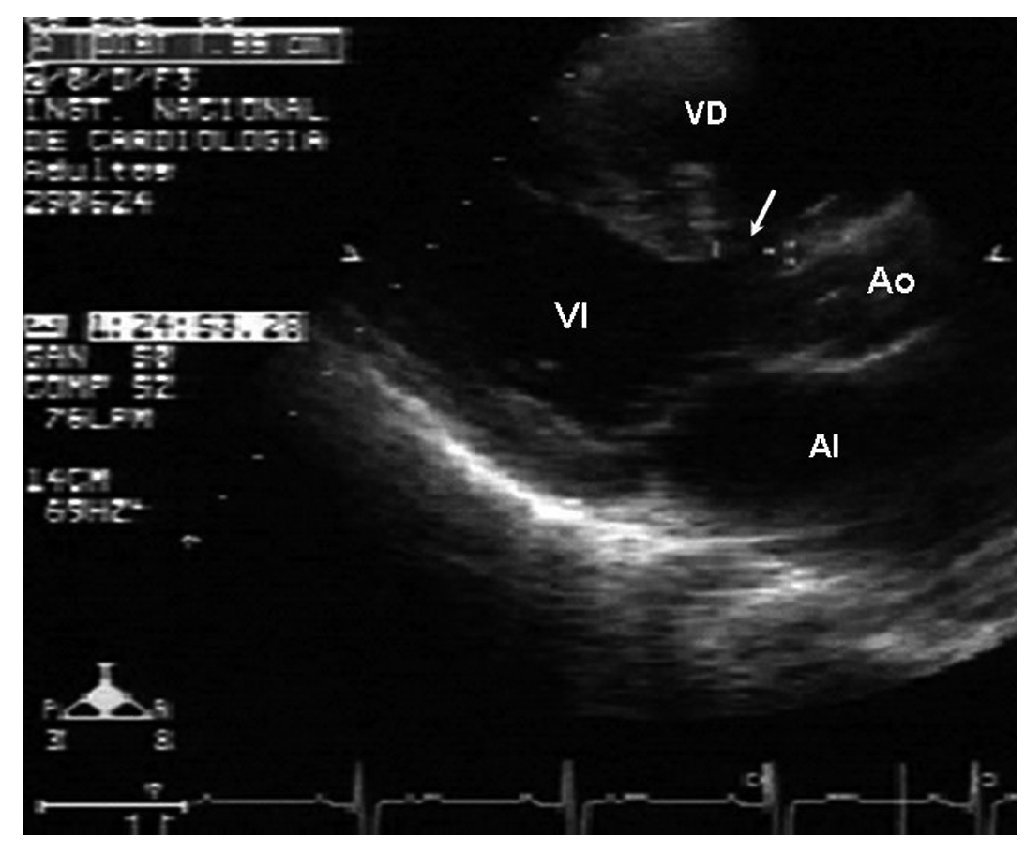

El electrocardiograma evidenció un crecimiento de las cavidades derechas. La radiografía de tórax demostró cardiomegalia en grado II a expensas de las cavidades derechas, el abombamiento del cono de la pulmonar, con aumento de la trama vascular pulmonar (fig. 1). Se realizó un ecocardiograma que evidenció una anomalía de Ebstein con adosamiento del 50 %, insuficiencia tricuspídea moderada, con datos de hipertensión arterial pulmonar y CIV muscular alta de 14 mm de diámetro (figs. 2 y 3). La función ventricular izquierda estaba conservada y presentaba dilatación del tronco y las ramas de la arteria pulmonar. Se realizó un cateterismo cardíaco con el fin de precisar las resistencias vasculares pulmonares. Se observaron una presión sistólica de la arteria pulmonar de 92 mmHg (media de 40 mmHg); un índice de resistencia pulmonar total de 12,7 U Wood, que con la administración de oxígeno disminuyó a 2,46 U Wood; presión sistólica aórtica de 95 mmHg (media de 60 mmHg); angiografía pulmonar magnificada con una mancha capilar heterogénea; arterias monopediales presentes y buen vaciamiento del medio de contraste (figs. 4 y 5). Se sometió a la paciente a tratamiento quirúrgico, con un tiempo de circulación extracorpórea de 111 min y de pinzamiento aórtico de 86 min. Se realizaron una plastia tricuspídea, la plicatura de la "porción auriculizada" del ventrículo derecho, el cierre directo de foramen oval y el cierre de la CIV con parche de pericardio bovino valvulado con fenestración de 6 mm. La estancia en la terapia posquirúrgica fue de 48 h; se la extubó en las primeras horas del postoperatorio, con apoyo inotrópico con milrinona y dobutamina. A las 72 h de la cirugía la paciente presentó una crisis convulsiva que se trató con diazepam. Se le realizaron una resonancia magnética de cráneo que no evidenció alteraciones y un ecocardiograma de control que mostró insuficiencia tricuspídea severa. Evolucionó con importante compromiso hemodinámico y requirió de mayor soporte inotrópico. Presentó varios episodios de arritmias, como taquicardia supraventricular y taquicardia ventricular y, finalmente, falleció a los 5 días posteriores a la cirugía.

Figura 2 Ecocardiograma en eje paraesternal largo bidimensional donde se observa la medición de la comunicación interventricular. AI: aurícula izquierda; Ao: aorta; VD: ventrículo derecho; VI: ventrículo izquierdo.